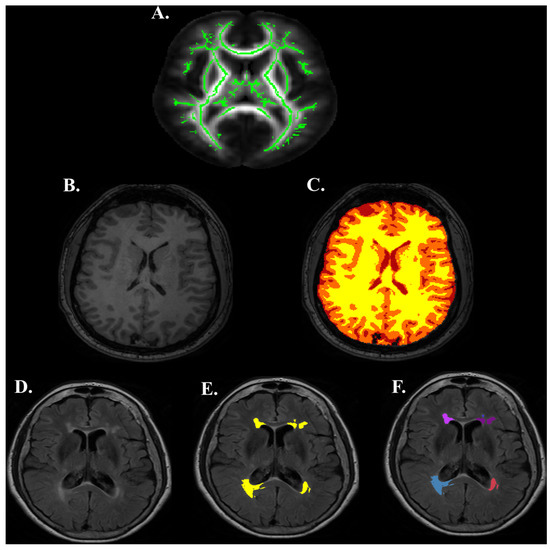

2.5. cfMRI Processing

2.6. Structural and Functional ROIs

2.7. Structural Images

2.8. Diffusion Images